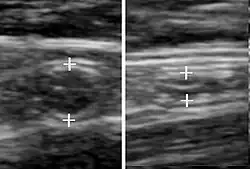

Abdominal ultrasonography, preferably with doppler sonography, is useful to detect appendicitis, especially in children. Ultrasound can show the free fluid collection in the right iliac fossa, along with a visible appendix with increased blood flow when using color Doppler, and noncompressibility of the appendix, as it is essentially a walled-off abscess. Other secondary sonographic signs of acute appendicitis include the presence of echogenic mesenteric fat surrounding the appendix and the acoustic shadowing of an appendicolith.[59] In some cases (approximately 5%),[60] ultrasonography of the iliac fossa does not reveal any abnormalities despite the presence of appendicitis. This false-negative finding is especially true of early appendicitis before the appendix has become significantly distended. Also, false-negative findings are more common in adults where larger amounts of fat and bowel gas make visualizing the appendix technically difficult. Despite these limitations, sonographic imaging with experienced hands can often distinguish between appendicitis and other diseases with similar symptoms. Some of these conditions include inflammation of lymph nodes near the appendix or pain originating from other pelvic organs such as the ovaries or Fallopian tubes. Ultrasounds may be either done by the radiology department or by the emergency physician.[61]

Ultrasound showing appendicitis and an appendicolith.[62]

Ultrasound showing appendicitis and an appendicolith.[62] -

Ultrasound of a normal appendix for comparison. -

A normal appendix without and with compression. Absence of compressibility indicates appendicitis.[59]